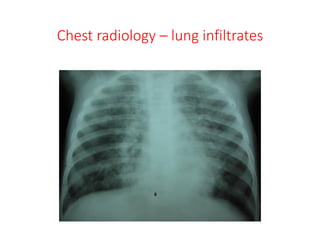

Chest radiology – lung infiltrates

Chest X - ray

Bronchopneumonia Lobar Pneumonia